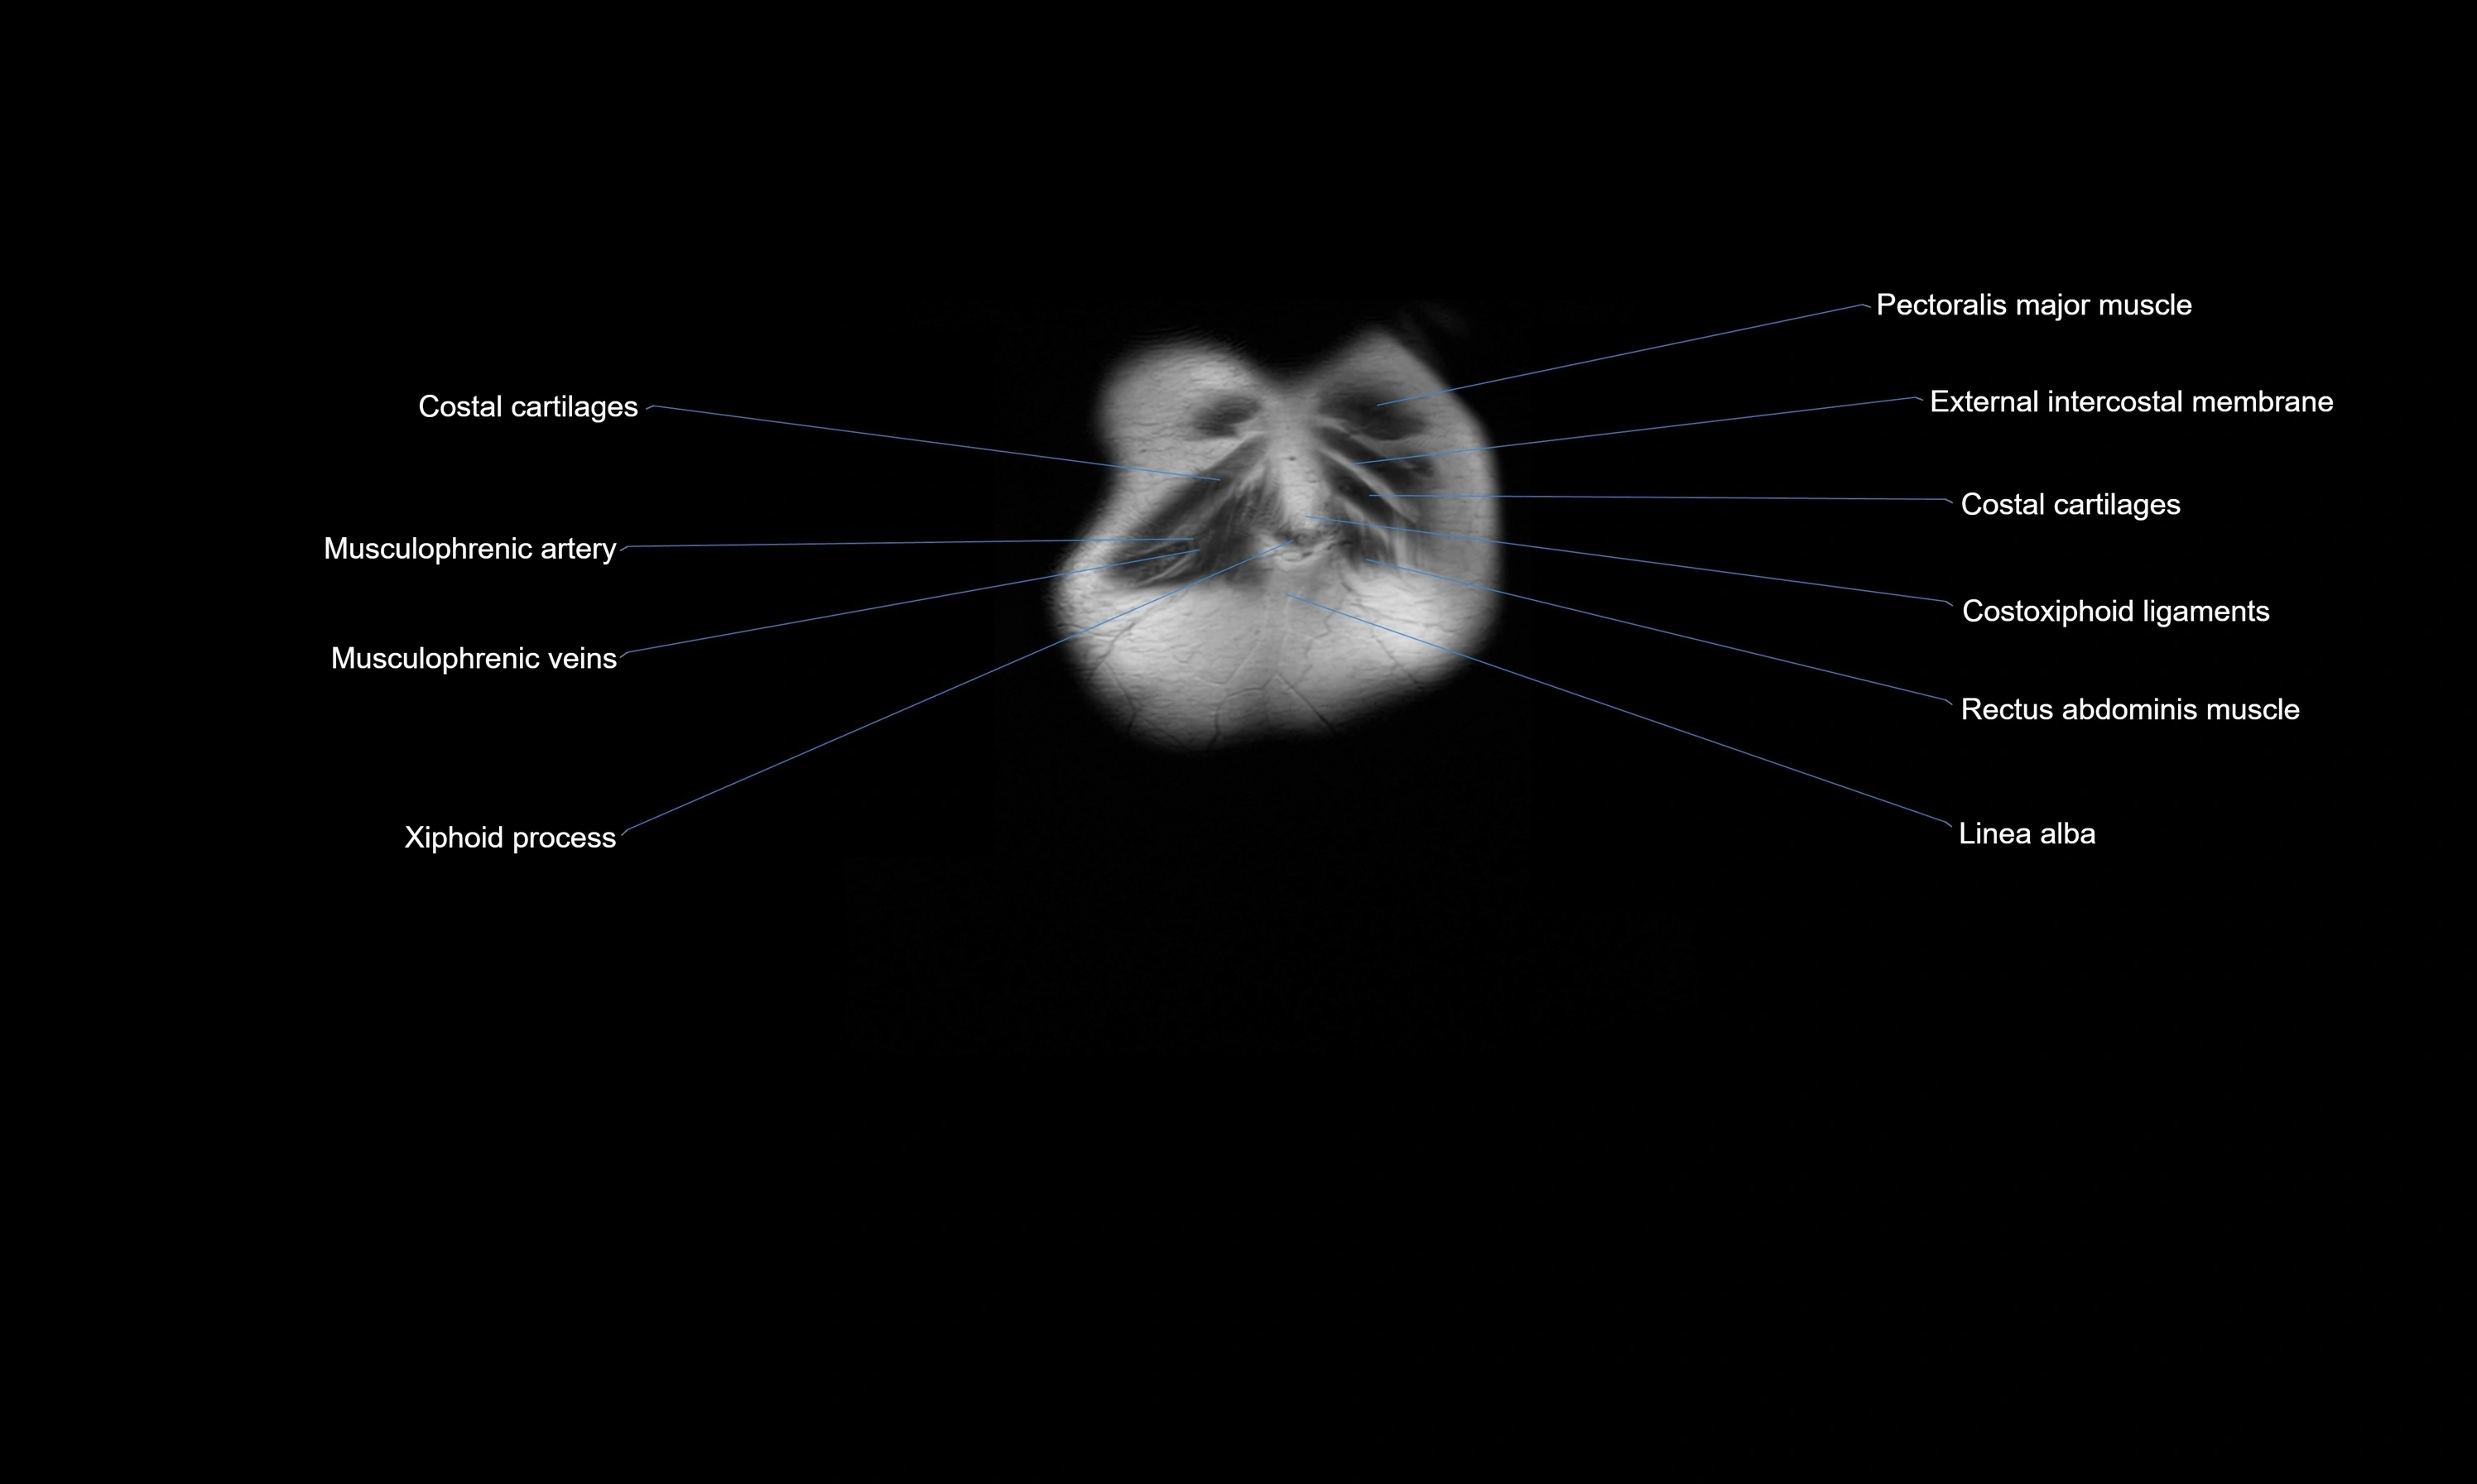

- Costochondral joints

- Linea alba

- Rectus abdominis muscle

- Transversus thoracis muscle